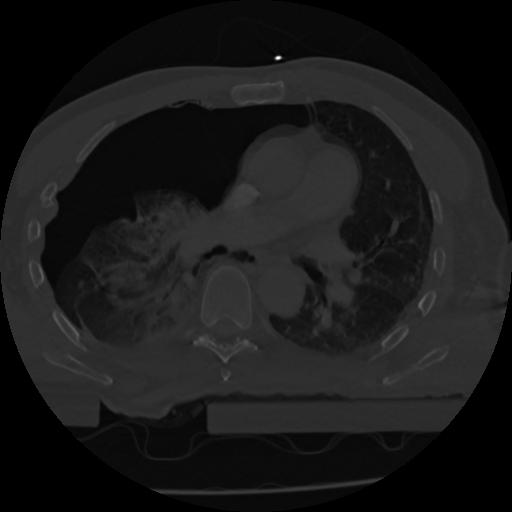

22 ANGIO,CE,Vol,0.5,ANGIO,,